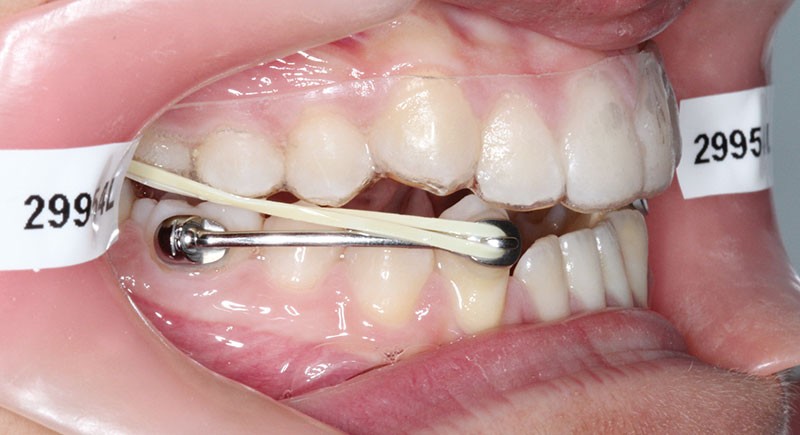

1re phase : recul des secteurs latéraux mandibulaires avec le Motion Classe III Carriere (fig. 4 à 6)

Nous mettons en place des bras latéraux Motion associés à des élastiques intermaxillaires ancrés sur des brackets sur 17 et 27 et une gouttière thermoformée maxillaire portée jour et nuit :

• 1er mois : élastiques 6 oz. 1/4”

• 2e mois et suivants : élastiques 6 oz.1/4“

L’objectif de cette étape est d’obtenir un recul des secteurs latéraux mandibulaires afin de positionner les molaires et canines en classe I et de réorienter le plan d’occlusion en haut en avant.